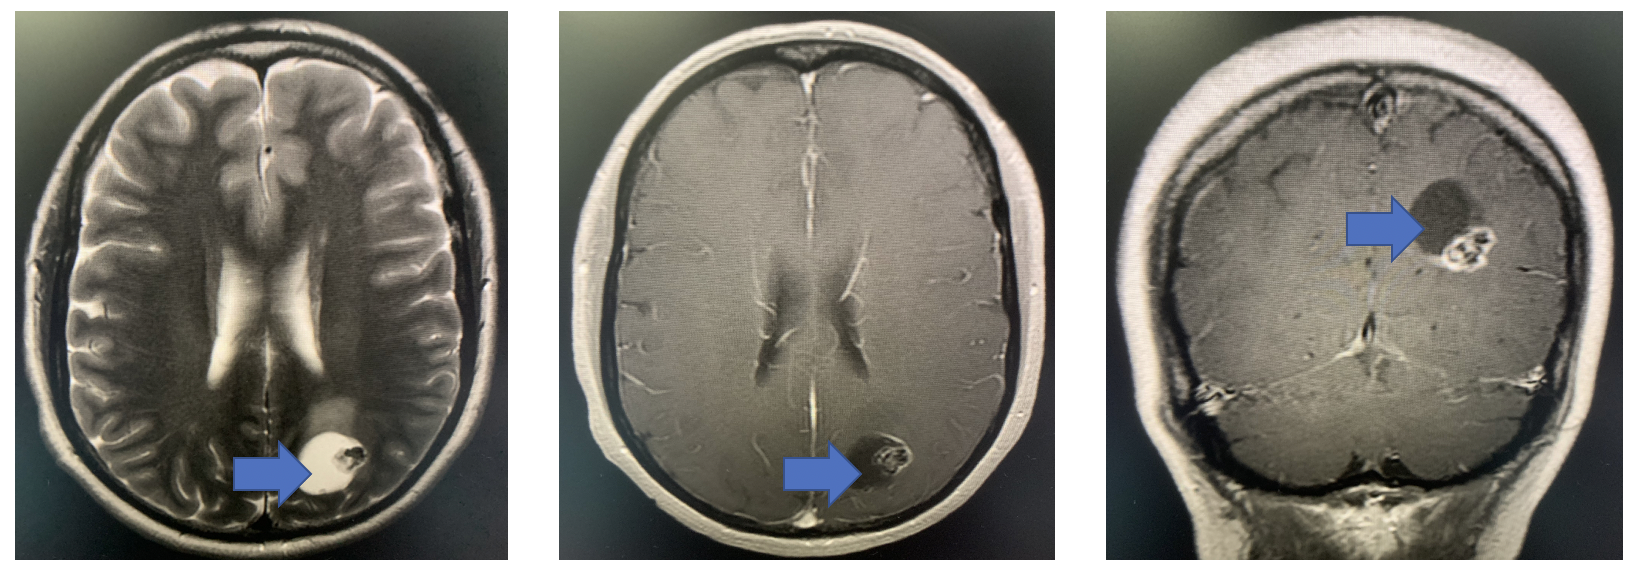

间变性星形细胞瘤,等你分析 | 读片专栏933期

图片尺寸958x803